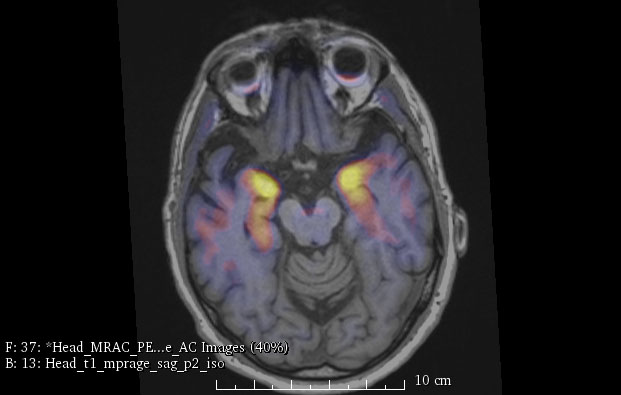

Attached is the first Positron Emission Tomography (PET) scan using a tracer for tau protein performed at UNC Hospital as part of a research study using one of only a handful of hybrid PET-MRI scanners in the country. This is a scan of a patient with Mild Cognitive Impairment, which shows tau protein binding selectively to the hippocampal regions, the memory-making part of the brain.